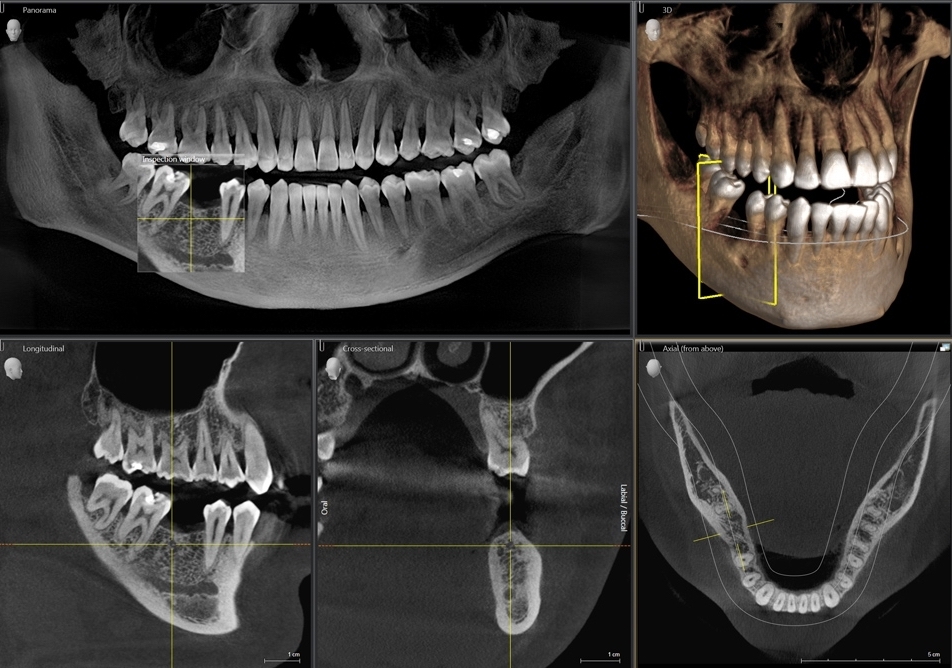

Кт 7180 3

Кт 7180 3 112 фотографий